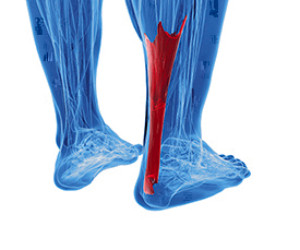

People who participate in sporting activities may experience Achilles tendon injuries. If it is torn, surgery may be necessary to repair the tendon, and a lengthy recovery period is often needed. The Achilles tendon is located in the back of the calf, and its purpose is to connect the heel to the calf muscles. It may become injured if sudden jumping or sprinting is performed. This may occur if certain sports are played that can include volleyball and basketball. There are existing conditions which could weaken the Achilles tendon. These can consist of diabetes, specific forms of arthritis that can include gout, or if certain medications are taken. The symptoms that are often associated with this condition can include difficulty in walking, and there may be severe pain while attempting to point and flex the foot. If you have endured an Achilles tendon injury, it is advised to speak with a podiatrist who can guide you toward the proper treatment.

People who participate in sporting activities may experience Achilles tendon injuries. If it is torn, surgery may be necessary to repair the tendon, and a lengthy recovery period is often needed. The Achilles tendon is located in the back of the calf, and its purpose is to connect the heel to the calf muscles. It may become injured if sudden jumping or sprinting is performed. This may occur if certain sports are played that can include volleyball and basketball. There are existing conditions which could weaken the Achilles tendon. These can consist of diabetes, specific forms of arthritis that can include gout, or if certain medications are taken. The symptoms that are often associated with this condition can include difficulty in walking, and there may be severe pain while attempting to point and flex the foot. If you have endured an Achilles tendon injury, it is advised to speak with a podiatrist who can guide you toward the proper treatment.

The Achilles tendon is a tendon that connects the lower leg muscles and calf to the heel of the foot. It is the strongest tendon in the human body and is essential for making movement possible. Because this tendon is such an integral part of the body, any injuries to it can create immense difficulties and should immediately be presented to a doctor.

The Achilles tendon is the strongest tendon in the human body. Its purpose is to connect the lower leg muscles and calf to the heel of the foot. This tendon is responsible for facilitating all types of movement, like walking and running. This tendon provides an enormous amount of mobility for the body. Any injuries inflicted to this tissue should be immediately brought up with a physician to prevent further damage.

The most common injuries that can trouble the Achilles tendon are tendon ruptures and Achilles tendinitis. Achilles tendinitis is the milder of the two injuries. It can be recognized by the following symptoms: inflammation, dull-to-severe pain, increased blood flow to the tendon, thickening of the tendon, and slower movement time. Tendinitis can be treated via several methods and is often diagnosed by an MRI.

An Achilles tendon rupture is trickier to heal, and is by far the most painful injury. It is caused by the tendon ripping or completely snapping. The results are immediate and absolutely devastating, and will render the patient immobile. If a rupture or tear occurs, operative and non-operative methods are available. Once the treatment begins, depending on the severity of the injury, recovery time for these types of issues can take up to a year.

Simple preventative measures can be taken as a means to avoid both injuries. Prior to any movement, taking a few minutes to stretch out the tendon is a great way to stimulate the tissue. Calf raises, squats, leg curls, leg extensions, leg raises, lunges, and leg presses are all suggested ways to help strengthen the lower legs and promote Achilles tendon health.

Many problems arise among athletes and people who overexert themselves while exercising. Problems can also happen among those who do not warm up properly before beginning an activity. Proper, comfortable shoes that fit correctly can also decrease tendon injuries. Some professionals also suggest that when exercising, you should make sure that the floor you are on is cushioned or has a mat. This will relieve pressure on the heels. A healthy diet will also increase tendon health.